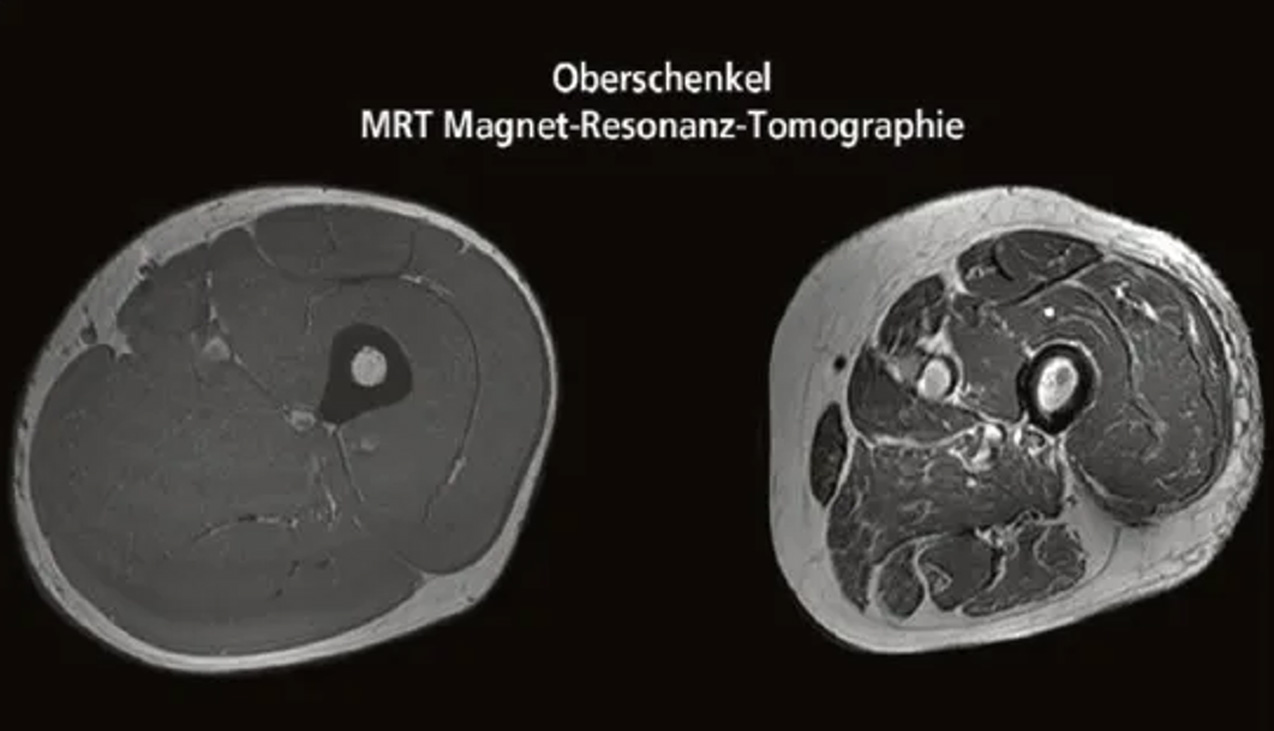

Vergleich des Oberschenkelquerschnitts eines 21-jährigen und eines 83-jährigen – weiss ist Fettgewebe

(Quelle: published online on 01.11.2019, https://doi.org/10.34045/SSEM/2014/25)